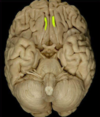

Fornix

Corpus callosum

Lateral ventricles